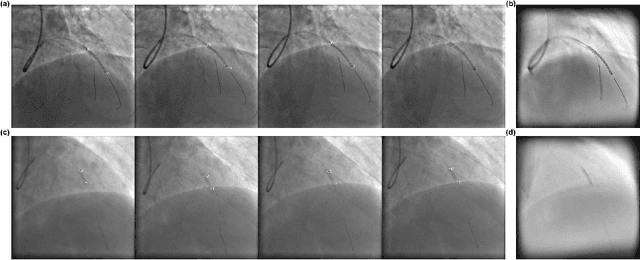

In clinical procedures of angioplasty (i.e., open clogged coronary arteries), devices such as balloons and stents need to be placed and expanded in arteries under the guidance of X-ray fluoroscopy. Due to the limitation of X-ray dose, the resulting images are often noisy. To check the correct placement of these devices, typically multiple motion-compensated frames are averaged to enhance the view. Therefore, device tracking is a necessary procedure for this purpose. Even though angioplasty devices are designed to have radiopaque markers for the ease of tracking, current methods struggle to deliver satisfactory results due to the small marker size and complex scenes in angioplasty. In this paper, we propose an end-to-end deep learning framework for single stent tracking, which consists of three hierarchical modules: U-Net based landmark detection, ResNet based stent proposal and feature extraction, and graph convolutional neural network (GCN) based stent tracking that temporally aggregates both spatial information and appearance features. The experiments show that our method performs significantly better in detection compared with the state-of-the-art point-based tracking models. In addition, its fast inference speed satisfies clinical requirements.